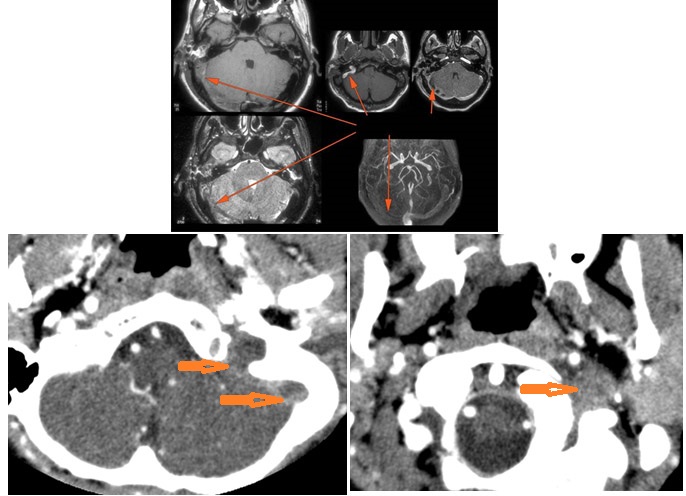

Intracranial

There is gas in the subarachnoid space or otherwise intracranial.

There is evidence of thrombosis, thrombophlebitis or other occlusive or inflammatory process of the sigmoid sinus, transverse sinus, the vein of Labbe’ or jugular bulb

There is evidence of thrombosis, thrombophlebitis or other occlusive or inflammatory process of jugular vein.

There is dural reactive change along the floor of the middle cranial fossa or along the inner surfaces of the petrous portion of the temporal bone.

There is a subperiosteal, subdural or epidural abscess along the floor of the middle cranial fossa or along the inner surfaces of the petrous portion of the temporal bone.

There is likely meningitis involving the inferior temporal lobe or adjacent cerebellum

There is likely cerebritis involving the inferior temporal lobe or adjacent cerebellum.

There is brain edema and/or evolving abscess present or, specifically, involving the inferior temporal lobe or adjacent cerebellum.

There is obstructive hydrocephalus - either intra or extra ventricular or signs of raised intracranial pressure.